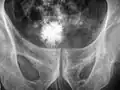

Kamień struwitowy